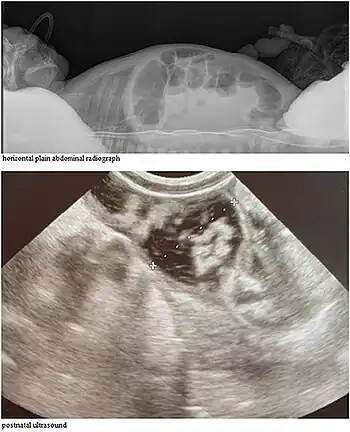

CCD may be detectable on prenatal ultrasound.[4][5]

After birth, signs in affected babies typically are abdominal distension, visible peristalsis, and watery stools persistent from birth that show chloride loss of more than 90 mmol/L.[5]